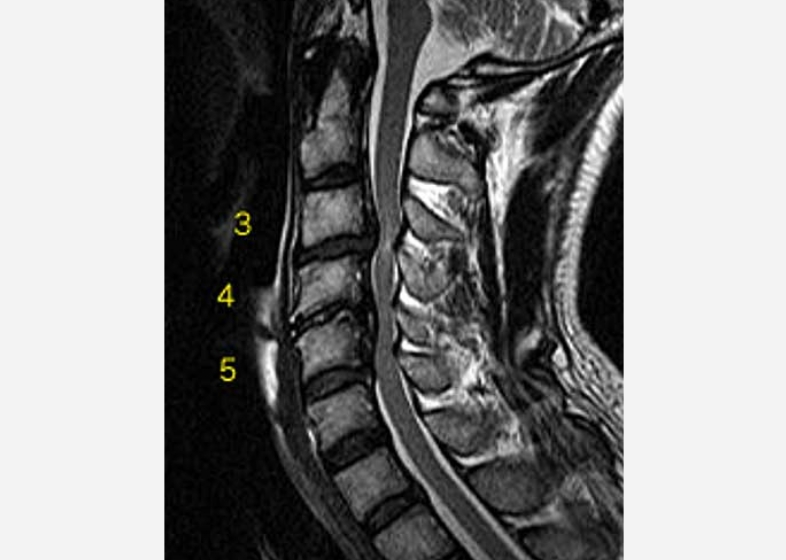

脊柱管狭窄症(頚椎) 43歳男性

手術前

第3~5頚椎に脊柱管狭窄症を認め、脊髄が圧迫されている